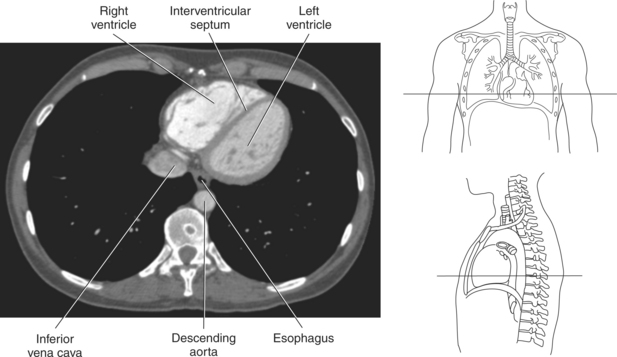

The walls of the heart consist of three layers: (1) epicardium, the thin outer layer that is in contact with the pericardium; (2) myocardium, the thick middle layer consisting of strong cardiac muscle; and (3) endocardium, the thin, endothelial layer lining the inner surface. The endothelial layer also lines the valves of the heart and is continuous with the inner lining of the blood vessels. The heart is divided into four chambers: the right and left atria and the right and left ventricles. The two superior collecting chambers called atria are divided by the interatrial septum. During embryonic development an oval opening exists within the interatrial septum called the foramen ovale. This opening allows blood flow between the right and left atria during fetal lung development. At birth, the foramen ovale closes, leaving a small depression in the septal wall called the fossa ovalis in the adult heart. The two inferior pumping chambers called ventricles are divided by the interventricular septum (Figure 6.39).

The right atrium forms the right border of the heart and receives deoxygenated blood from the body via the superior and inferior venae cavae and from the coronary sinus and cardiac veins that drain the myocardium. A small muscular embryonic appendage, the right auricle, projects upward and toward the left from the right atrium, covering the root of the aorta (Figure 6.40). The right ventricle lies on the diaphragm and comprises the largest portion of the anterior surface of the heart. It receives deoxygenated blood from the right atrium and forces it into the pulmonary trunk for conveyance to the lungs. Projecting off the inferior surface of the ventricular walls are conical-shaped projections of cardiac muscle called papillary muscles that anchor the cusps of the tricuspid valve to the right ventricle (Figure 6.39). The left atrium lies posterior to the right atrium and is the most posterior surface of the heart. It also has an embryonic appendage, the left auricle, that projects to the left of the pulmonary trunk over the superior surface of the heart. The left atrium receives oxygenated blood directly from the lungs via the four pulmonary veins (two on each side). The left ventricle forms the apex, left border, and most of the inferior surface of the heart. It receives oxygenated blood from the left atrium and pumps it into the aorta for distribution throughout the systemic circuit. The myocardium of the left ventricle is normally three times thicker than that of the right ventricle, reflecting the force necessary to pump blood to the distant sites of the systemic circulation (Figures 6.41 through 6.52). Two papillary muscles project from the ventricular walls to anchor the bicuspid valve to the ventricle (Figures 6.39 and 6.47).

Blood travels to and from the heart through the great vessels, which include the aorta, pulmonary arteries and veins, and superior and inferior venae cavae (Figures 6.54 and 6.55). The aorta is the largest artery of the body and can be divided into the ascending aorta, aortic arch, and descending aorta. The ascending aorta begins at the base of the left ventricle at the level of the sternal angle, then curves superiorly and posteriorly as the aortic arch over the root of the left lung. The top of the aortic arch is approximately at T3 (Figures 6.56 and 6.57). The arch continues as the descending aorta posterior to the left bronchus and pulmonary trunk, on the left side of the vertebral body of T4 (Figures 6.58 and 6.59). The descending aorta passes slightly anterior and to the left of the vertebral column as it descends through the thoracic and abdominal cavities (Figure 6.60). While in the thoracic cavity, the descending aorta is commonly called the thoracic aorta, and while in the abdominal cavity, it is called the abdominal aorta. The pulmonary trunk is the origin of the right and left pulmonary arteries and lies entirely within the pericardial sac. It arises from the right ventricle and ascends in front of the ascending aorta, courses posteriorly and to the left, where it bifurcates at the level of the sternal angle (T4) into the right and left pulmonary arteries (Figures 6.61 through 6.63). The pulmonary trunk is attached to the aortic arch by a fibrous cord called the ligamentum arteriosum, the remnant of an important fetal blood vessel (ductus arteriosus) that links the pulmonary and systemic circuits during fetal development (Figures 6.54 and 6.61). The right pulmonary artery courses laterally, posterior to the ascending aorta and superior vena cava, and anterior to the esophagus and right mainstem bronchus, to the hilum of the right lung. At the root of the right lung, the right pulmonary artery divides into two branches, with the lower branch supplying the middle and inferior lobes and the upper branch supplying the superior lobe (Figures 6.61 through 6.64). The left pulmonary artery, shorter and smaller than the right, is also the most superior of the pulmonary vessels. It travels horizontally, arching over the left mainstem bronchus, and enters the hilum of the left lung just superior to the left mainstem bronchus (Figures 6.61 through 6.64). Within the lungs, each pulmonary artery descends posterolateral to the main bronchus and divides into lobar and segmental arteries, continuing to branch out and to follow along with the smallest divisions of the bronchial tree (Figures 6.61 and 6.64). Located inferior to the pulmonary arteries are the four pulmonary veins, two each (superior and inferior) extending from each lung to enter the left atrium (Figures 6.54, 6.55, 6.61, and 6.64 through 6.68). They commence in a capillary network along the walls of the alveoli, where they are continuous with the capillaries of the pulmonary arteries. The venous capillaries merge to form small vessels that unite successively to eventually form a single trunk for each lobe: three for the right and two for the left lung. Frequently the trunk from the middle lobe of the right lung unites with the trunk from the upper lobe, forming just two trunks on the right side prior to entering the left atrium. The right superior pulmonary vein collects blood from the upper lobe segments of the right lung and passes anterior and inferior to the right pulmonary artery, behind the superior vena cava. The right inferior pulmonary vein receives blood from the right lower lobes of the lung and crosses behind the right atrium to the left atrium (Figures 6.61 and 6.69 through 6.71). The left superior pulmonary vein receives blood from the left upper lobe of the left lung and courses anterior and inferior to the left main bronchus as it enters the left atrium. The left inferior pulmonary vein drains the inferior lobe of the left lung and passes toward the left atrium anterior to the bronchi (Figures 6.61 and 6.72 through 6.74). The pulmonary veins course more horizontally than the pulmonary arteries and are ultimately oriented toward the left atrium. At the root of the lungs, the pulmonary veins are anterior to the pulmonary arteries, which are anterior to the bronchus. While within the lungs, the branches of the pulmonary arteries are anterior to the bronchi, which are anterior to the pulmonary veins. The superior and inferior venae cavae are the largest veins of the body. The superior vena cava is formed by the junction of the brachiocephalic veins, posterior to the right first costal cartilage, and carries blood from the thorax, upper limbs, head, and neck (Figure 6.24). As it travels inferiorly, it is located posterior and lateral to the ascending aorta before entering the upper portion of the right atrium (Figures 6.54 through 6.59). The inferior vena cava is formed by the junction of the common iliac veins in the pelvis and ascends the abdomen to the right of the abdominal aorta and anterior to the vertebral column. It passes through the caval hiatus of the diaphragm and almost immediately enters the inferior portion of the right atrium (Figures 6.75 and 6.76).